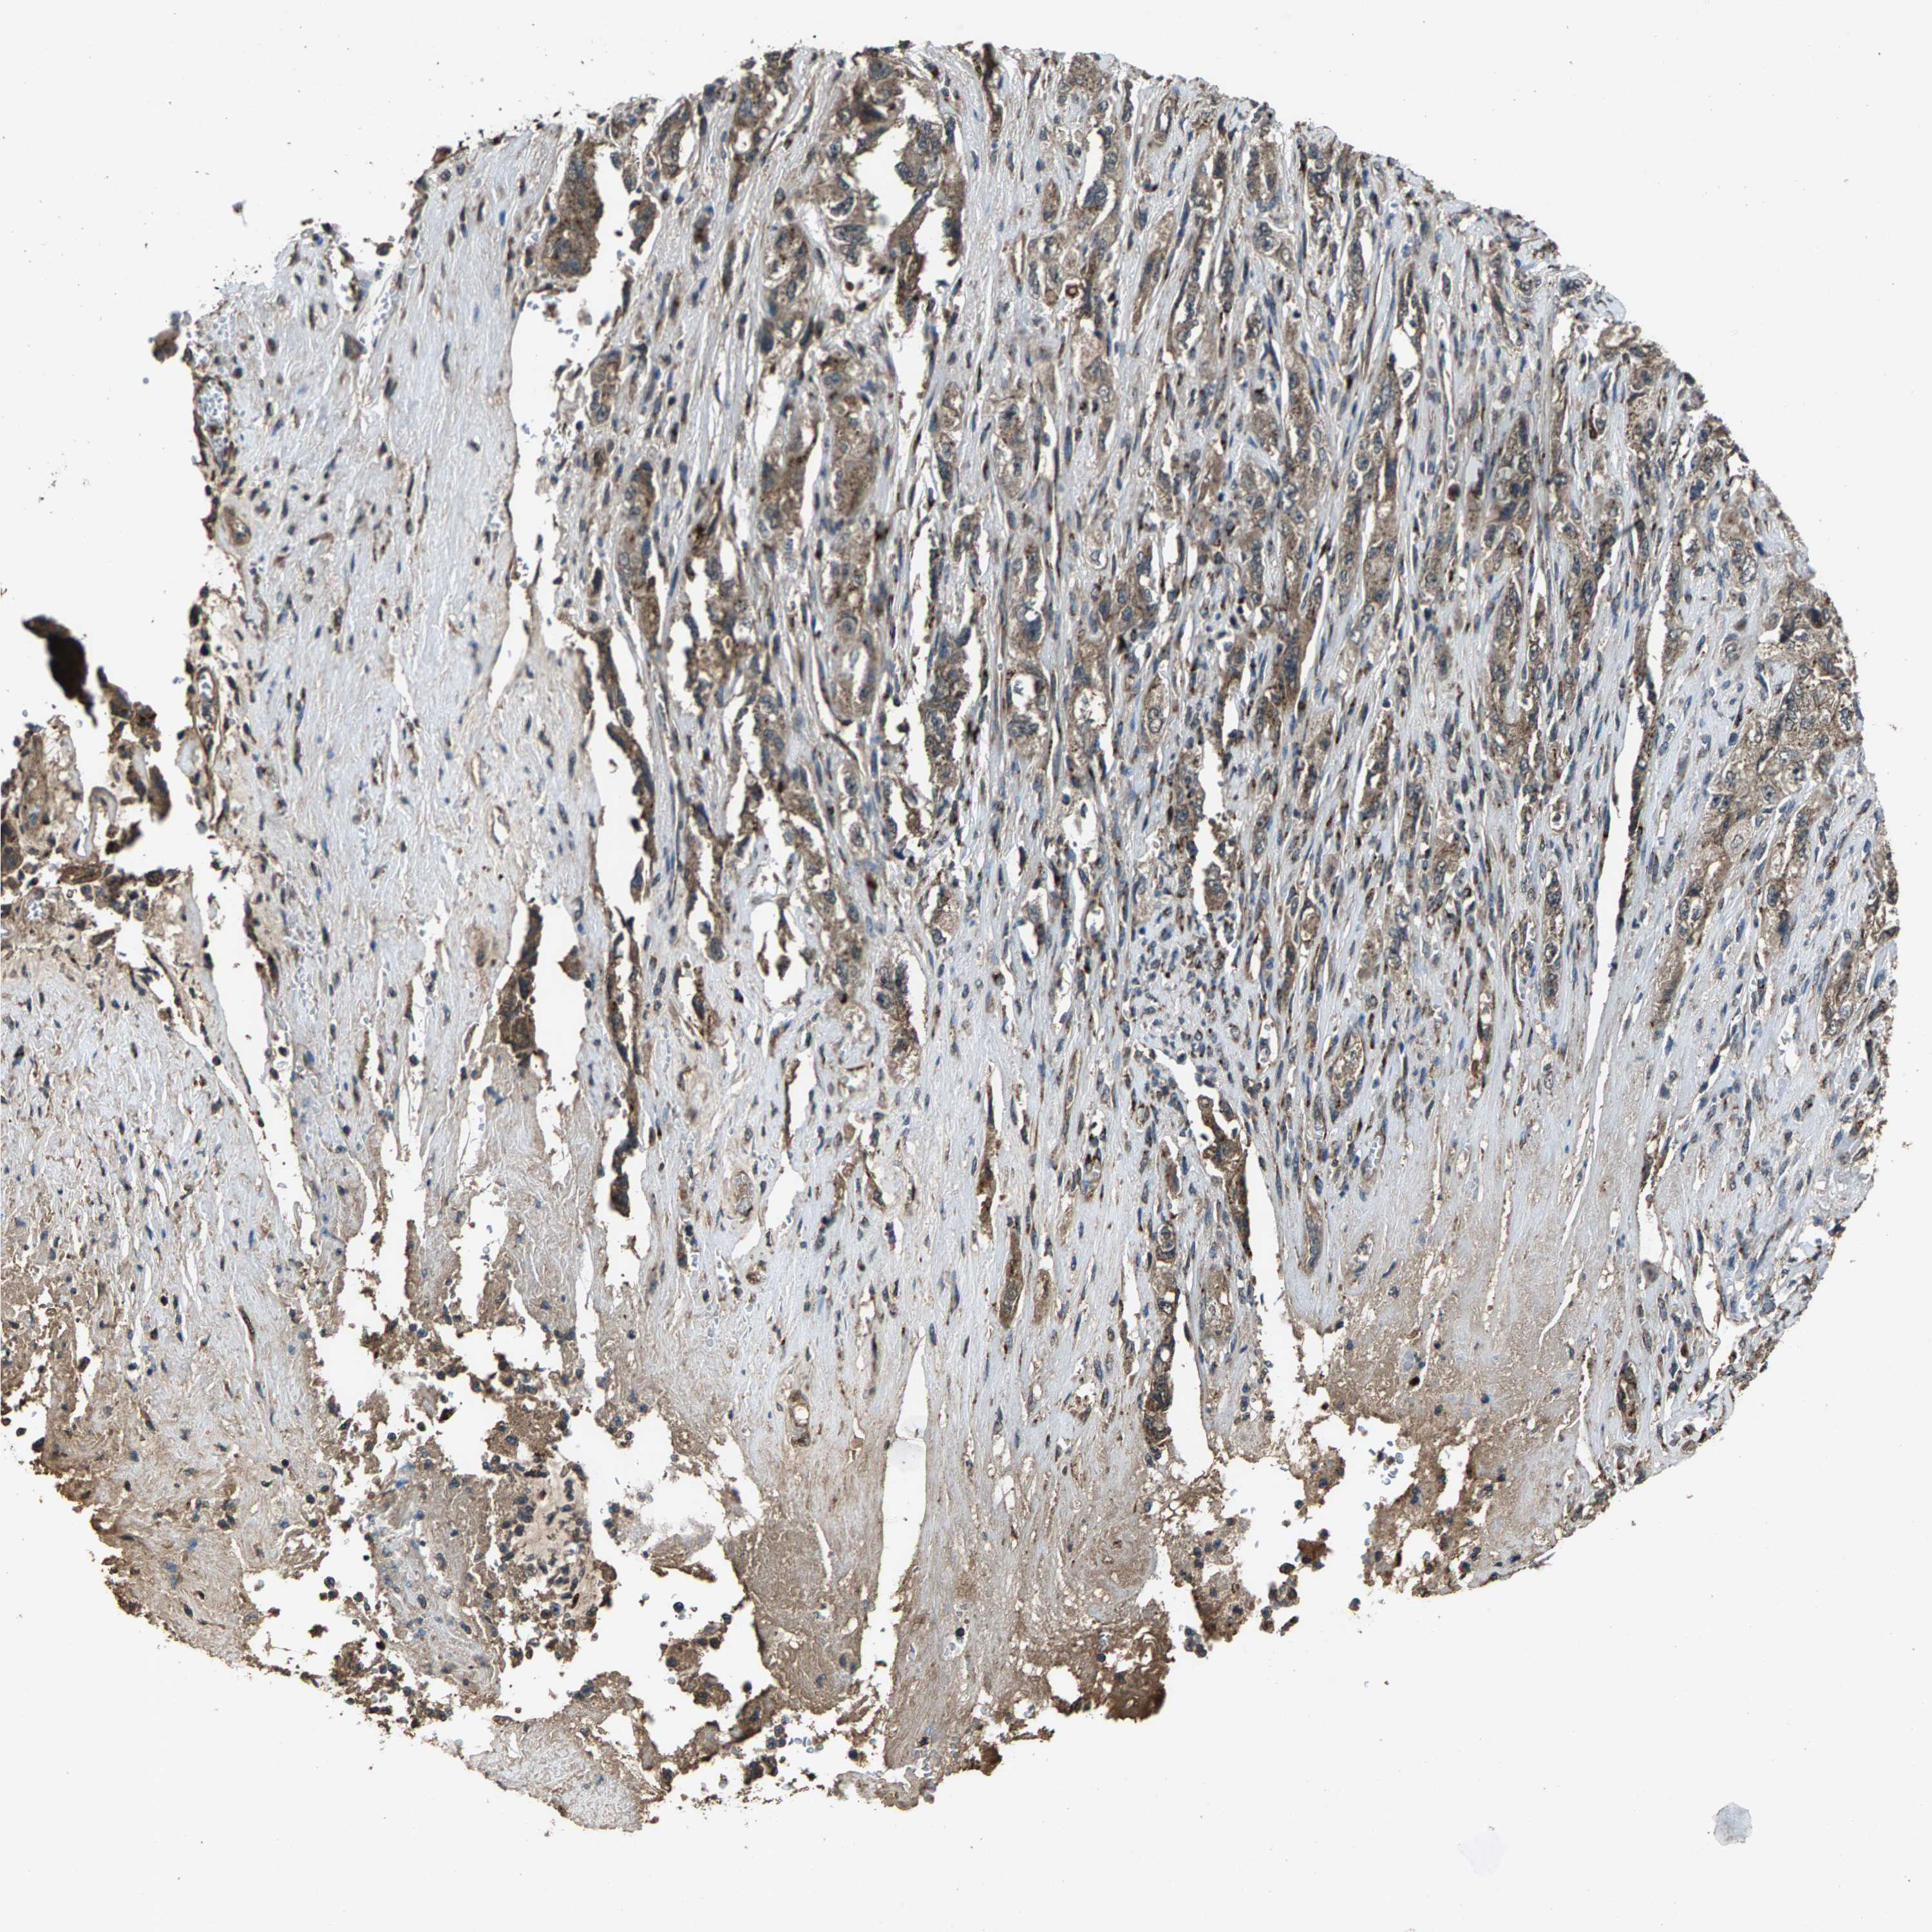

PANCREATIC CANCER - Protein expressioni

A mouse-over function shows sample information and annotation data. Click on an image to view it in a full screen mode. Samples can be filtered based on level of antibody staining by selecting one or several of the following categories: high, medium, low and not detected. The assay and annotation is described here.

Note that samples used for immunohistochemistry by the Human Protein Atlas do not correspond to samples in the TCGA dataset.

Antibody stainingi

Antibody staining in the annotated cell types in the current human tissue is reported as not detected, low, medium, or high, based on conventional immunohistochemistry profiling in selected tissues. This score is based on the combination of the staining intensity and fraction of stained cells.

Each image is clickable and will lead to virtual microscopy that enables deeper exploration of all samples and also displays staining intensity scores, fraction scores and subcellular localization as well as patient and tissue information for each sample.

Antibody HPA021374

Antibody HPA023161

Antibody HPA024631

Staining

High

Medium

Low

Not detected

Intensity

Strong

Moderate

Weak

Negative

Quantity

>75%

75%-25%

<25%

None

Location

Nuclear

Cytoplasmic/membranous

Cytoplasmic/membranous,nuclear

Adenocarcinoma, NOS